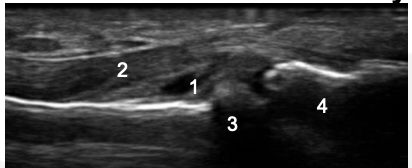

What is the abnormality?

1: Synovium, 2: Flexon Tendon, 3: Proximal Phalanx, 4: Middle Phalanx

1: Synonym, 2: Flexor Tendon; 3: Osteophyte